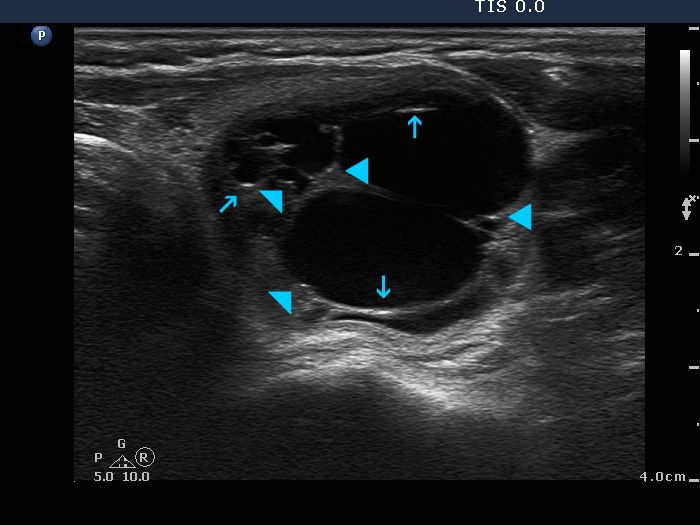

Benign cystic lesion (cytological diagnosis) - case 1139

The posterior acoustic enhancement in the dorsal wall of the small cystic areas causes no concern if this optical artifact is linear (arrows), however granular figures might be misinterpreted as punctate echogenic foci (microcalcifications) (arrowheads).